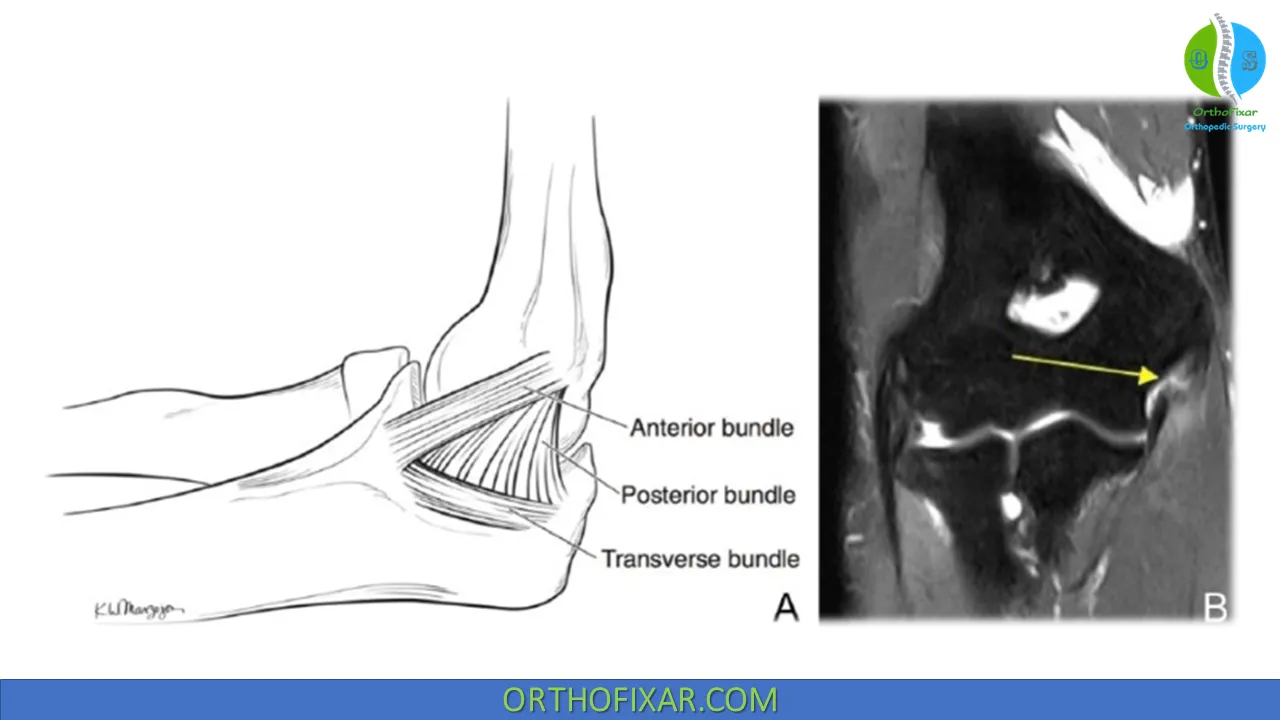

يُعد الرباط الجانبي الزندي (UCL) في الكوع بنية تشريحية حيوية تقع على الجانب الداخلي للمرفق، وتلعب دورًا محوريًا في استقرار المفصل. إنه أحد الأربطة الرئيسية التي تقاوم قوى الإجهاد الأروح (valgus stress) التي قد تدفع الساعد بعيدًا عن الجسم. غالبًا ما يتعرض هذا الرباط للإصابة لدى الرياضيين الذين يمارسون رياضات تتطلب حركات رمي متكررة وعالية السرعة، مثل لاعبي البيسبول وكرة المضرب والرمح، وكذلك نتيجة للصدمات المباشرة أو السقوط. تتراوح شدة إصابات الرباط الجانبي الزندي من الالتواءات الخفيفة (الدرجة الأولى) إلى التمزقات الجزئية (الدرجة الثانية) أو التمزقات الكاملة (الدرجة الثالثة).